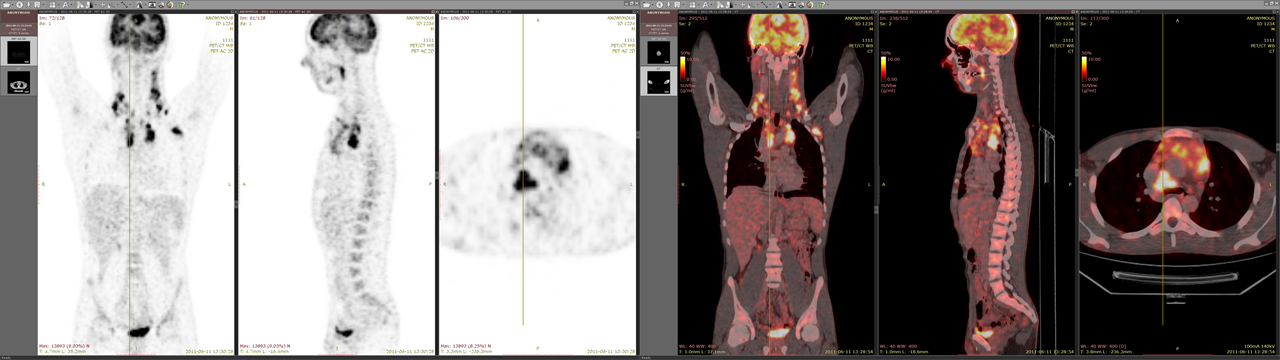

在双显示器上显示的 PET-CT 融合图像

当同一检查的序列在两个不同窗口中打开时,它们会自动同步;参考线(如适用)也会显示;图像融合同样可行。这对于在多显示器环境中浏览同一检查的序列非常有用。